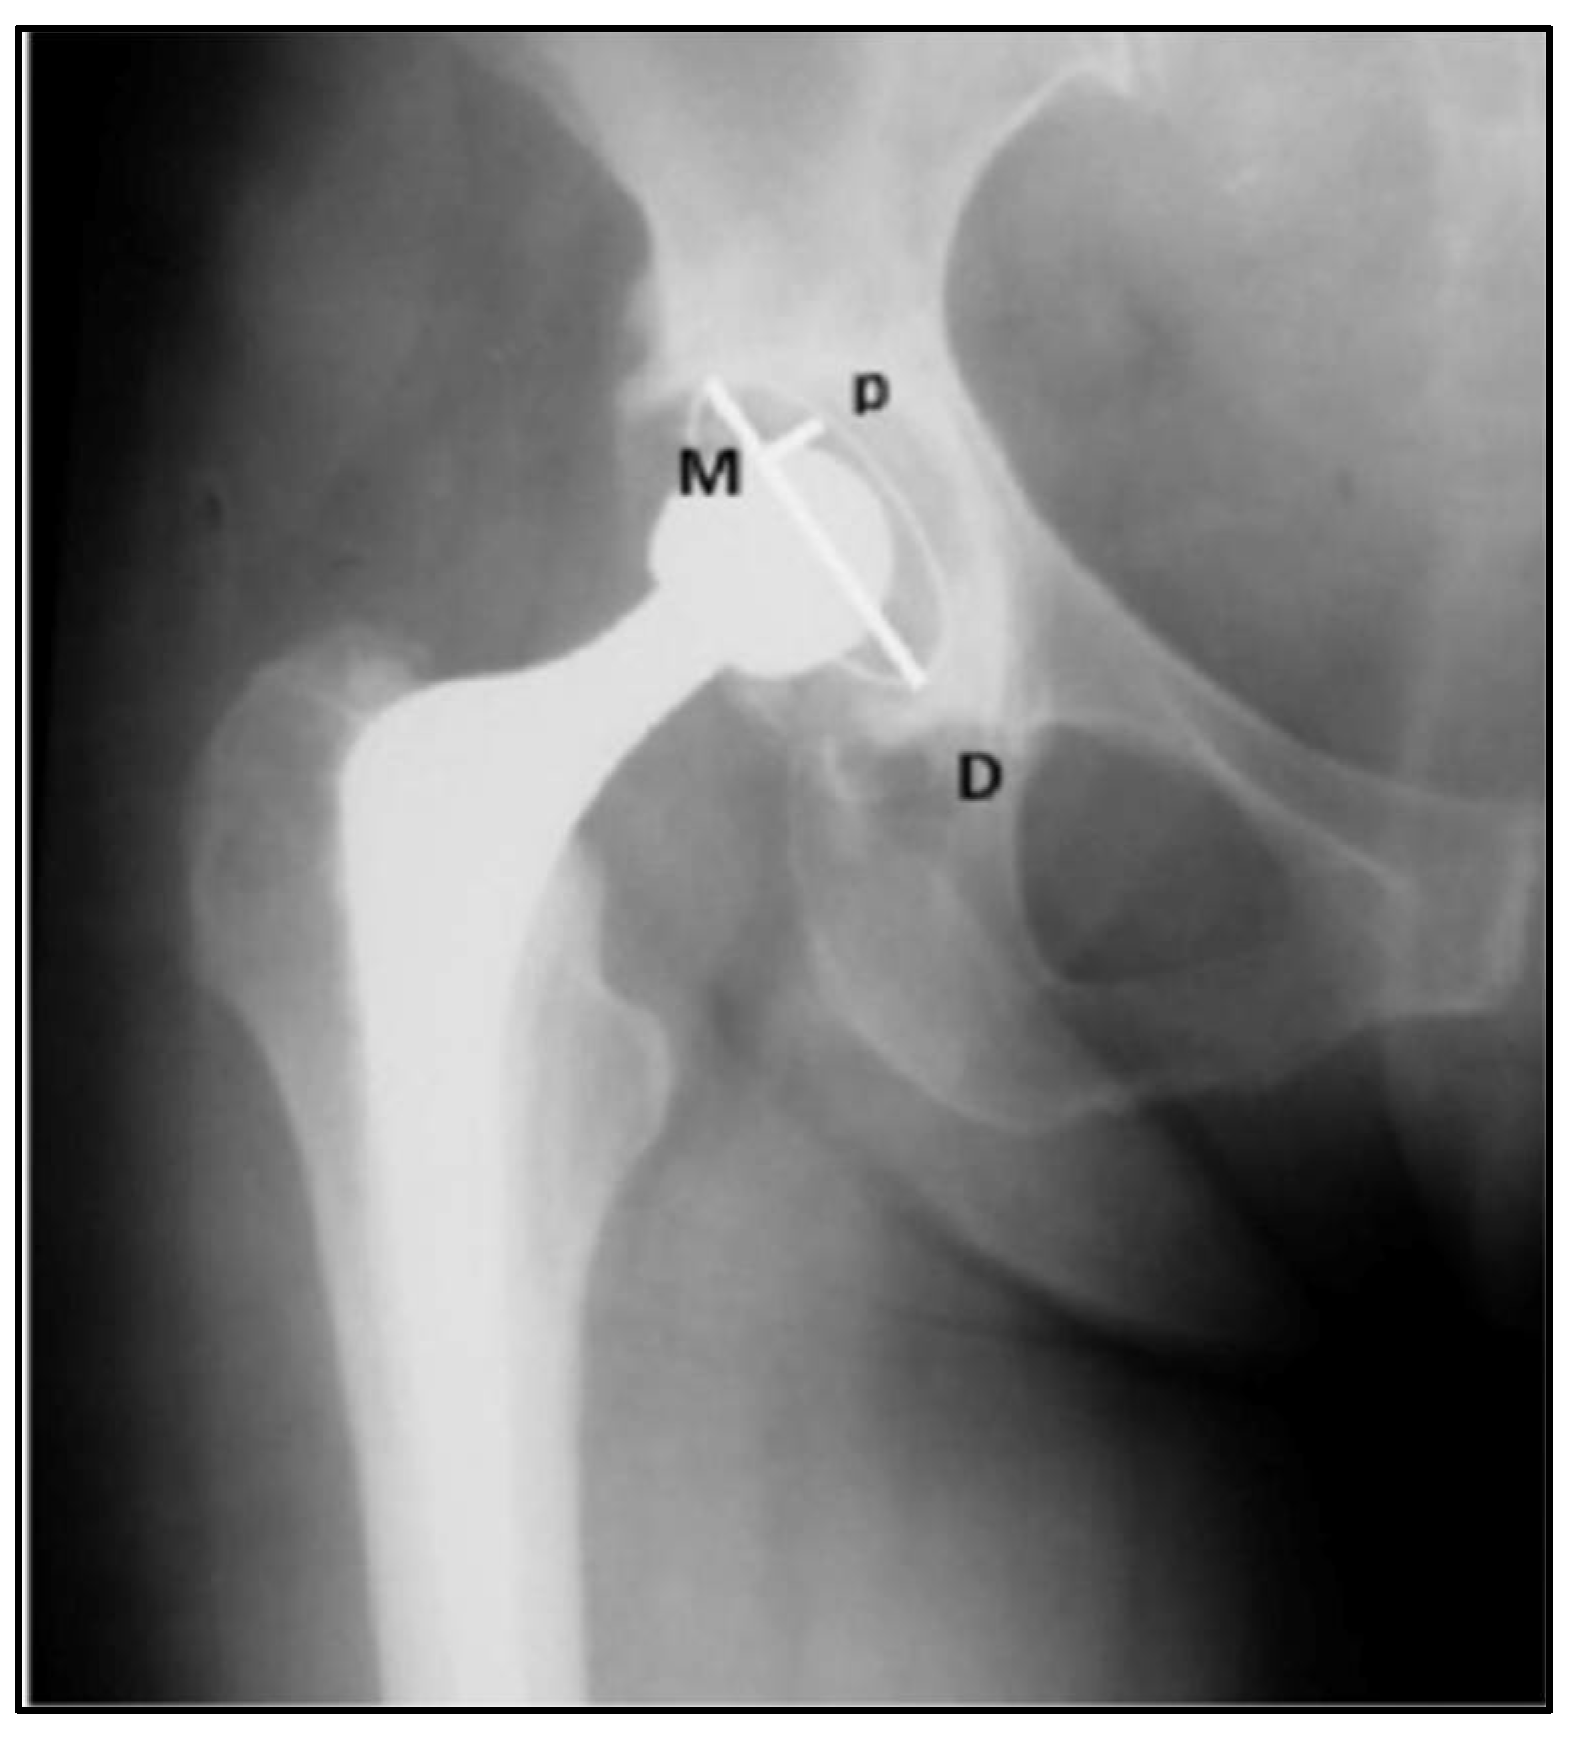

| Acetabular placement (degrees) | 44.3 ± 5.9 | 44.4 ± 6.3 | 0.083 |

| Implant Femoral Offset (cm) | 4.5 ± 0.7 | 4.5 ± 0.6 | 0.102 |